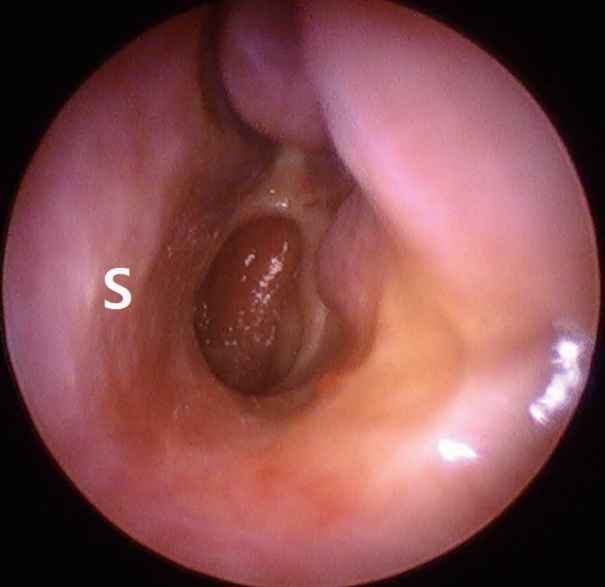

종물의 완전한 절제를 위하여 전신마취 후 비내시경을 이용한 종물 절제술(endoscopic mass excision)을 시행하기로 계획하였다. 하비갑개로 인해 종물의 기시부를 확인하는 데 제한이 있어, 하비갑개의 후방부 일부분을 절제하였다. 종물은 하비갑개의 후하방에서 기원하는 것을 확인하였고(Fig. 4), sickle knife와 cutting forceps을 가지고 주변 점막을 포함하여 완전 절제를 시행 후 재발 방지를 위해 종물의 기시부에 전기 소작을 시행하고 수술을 종료하였다. 종물의 크기는 2.0×0.8 cm이었으며 조직 병리 검사 결과는 점막하층의 부종과 호산구 및 형질세포의 침윤이 관찰되는 염증성 비용으로 최종 진단되었다(Fig. 5).

Fig. 1.Preoperative endoscopic findings. A bizarre single polypoid mass (*) is located between the left inferior turbinate and the basal floor of the nasal cavity. S: septum, IT: inferior turbinate. Fig. 2. Preoperative CT findings. Axial (A) and coronal (B) view. CT shows soft tissue density at the basal floor of the nasal cavity. Bone erosion is not observed and paranasal sinus is clear. Fig. 3.Preoperative MRI findings. Axial (A) and coronal (B) view. An ovoid homogenous enhancing mass (arrowhead) appears to originate from the posterior inferior side of the left inferior turbinate (arrow) and extends to the choana. Fig. 4. Operative findings. A pedicle (arrow) of single polypoid mass (*) is attached to the posterior side of the inferior turbinate. REFERENCES1. Lopatin A, Bykova V, Piskunov G. Choanal polyps: One entity, one surgical approach? Rhinology 1997;35(2):79-83.